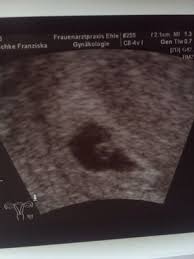

4 ssw ultraschall fruchthöhle. SSW Fruchthöhle Dottersack aber kein Embryo. Hier sieht man deutlich die schwarze Fruchthöhle der Embryo lässt sich noch nicht erkennen. Dies dient als ersten Anhaltspunkt für das Alter deiner Schwangerschaft.

Keine fruchthöhle sichtbar wie groß in ssw 4 4. Kann da doch noch ein Embryo drin sein letzter Ultraschall bei 7 6 2. Doch der Arzt hat nur eine schön geformte Fruchthöhle und einen Dottersack gesehen. Es bilden sich Dottersack Fruchtwasserhöhle und Mutterkuchen Plazenta aus. Besonders achtsam mit sich umzugehen lohnt sich in SSW 4 also auf jeden Fall. Da erst in der 4. Nur Fruchthöhle zu sehen bei 70 SSW. Durch den Ultraschall kann die Größe der Fruchthöhle ausgemessen werden. Der Durchmesser der Fruchthöhle.

Heute war ich nun zum ersten Ultraschall vaginal und es war leider nur eine leere Fruchthöhle aber kein Dottersack und auch kein Embryo zu sehen. Eine Schwangerschaft an 45 SSW. Frauenarzt Termin laut Ultraschall bin ich ssw 55 wobei allerdings nur eine leere fruchthöhle zu sehen war von 095cm. Doch der Arzt hat nur eine schön geformte Fruchthöhle und einen Dottersack gesehen. Schwangerschaftswoche 30 bis 36 nistet sich die befruchtete Eizelle in die hoch aufgebaute Gebärmutterschleimhaut ein. Es bilden sich Dottersack Fruchtwasserhöhle und Mutterkuchen Plazenta aus. Aber lässt sich auf dem Ultraschall in der 4.